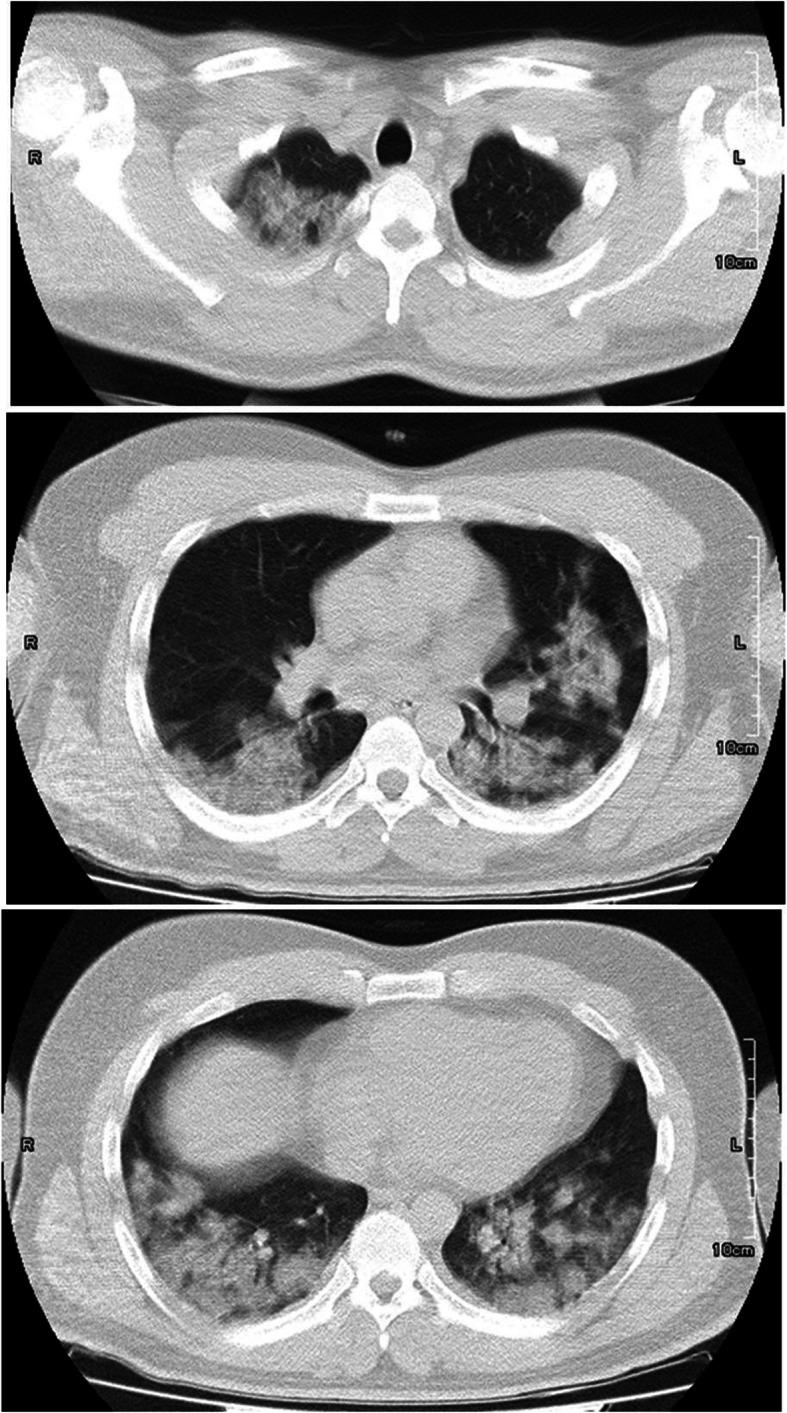

In December 2019, the World Health Organization (WHO) announced a series of pneumonia cases caused by an unknown origin, discovered in Wuhan, China. A dangerous virus called severe acute respiratory syndrome coronavirus 2 (SARS-CoV-2) caused a disease named acute respiratory syndrome, which was later popularly called coronavirus infection (COVID-19). Patients with acute COVID-19 are at high risk of thrombosis in various blood vessels due to hypercoagulability, blood stasis, and endothelial damage. In this study, we present a case report of a patient with COVID-19, who was hospitalized in one of the hospitals in Sanandaj, Iran. There were symptoms of fever, chills, muscle aches, cough, and tachycardia. Laboratory tests showed high levels of CRP, ESR, Ferritin CLIA, LDH and D-Dimer in this patient. Doppler ultrasound of the patient also revealed an abnormal finding, thrombosis in the right greater saphenous vein. This suggests that COVID-19 may lead to other negative effects through damage to blood vessels.

2019年12月,世界卫生组织(WHO)宣布在中国武汉发现了一系列由不明原因引起的肺炎病例。一种名为严重急性呼吸综合征冠状病毒2(SARS-CoV-2)的危险病毒引发了一种名为急性呼吸综合征的疾病,该疾病后来被普遍称为冠状病毒感染(COVID-19)。由于高凝性、血流淤滞和内皮损伤,急性COVID-19患者在各种血管中发生血栓形成的风险很高。在本研究中,我们报告了一例COVID-19患者的病例,该患者在伊朗萨南达杰的一家医院住院。患者出现发热、寒战、肌肉疼痛、咳嗽和心动过速等症状。实验室检查显示该患者的CRP、ESR、铁蛋白CLIA、LDH和D-二聚体水平升高。该患者的多普勒超声检查也发现了异常情况,即右侧大隐静脉血栓形成。这表明COVID-19可能通过损害血管导致其他负面影响。